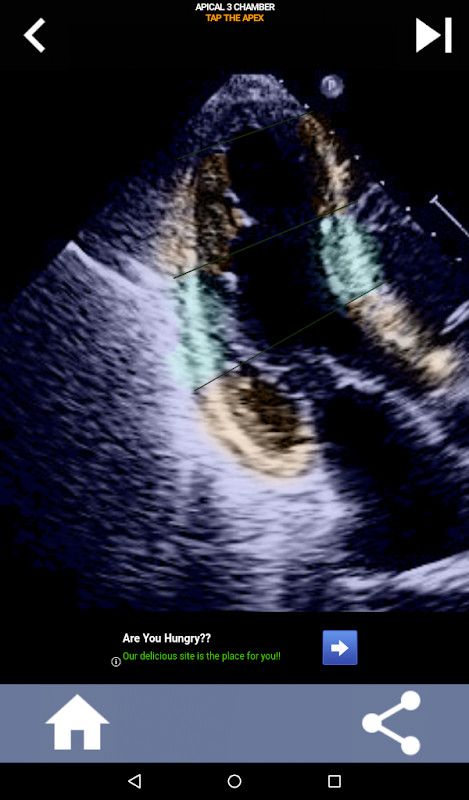

एएचए हृदय खंडों को सीखने के लिए प्रश्नोत्तरी-आधारित दृश्य दृष्टिकोण: इकोकार्डियोग्राफी

यह ऐप वास्तविक इको छवियों का उपयोग करके आपके ज्ञान का परीक्षण करेगा, जो मुझे अक्सर सबसे अच्छी शिक्षण पद्धति लगती है।